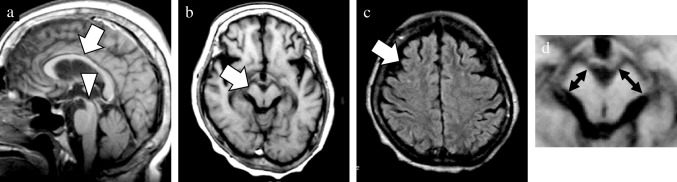

In addition to the well-established GCA and MTA scales, newly devised rating scales were utilized to evaluate the presence of midbrain atrophy and asymmetric atrophy. The degree of midbrain atrophy was assessed using a three-point scale (0 = normal, 1 = mild, and 2 = severe) primarily on sagittal T1WIs (Fig. 1). Mild midbrain atrophy indicated a slight reduction in the anteroposterior and/or superoinferior diameters. By contrast, a definitive decrease in these diameters was classified as severe midbrain atrophy. The degree of asymmetry in the frontal, temporal, parietal, and occipital lobes, along with the cerebral peduncle, was assessed using a three-point scale (0 = normal, 1 = mild, and 2 = severe) on axial T1WIs (Fig. 2). Severe asymmetry indicated the definite dilation of the sulcus and/or narrowing of the gyrus between the two hemispheres. Conversely, a case with unremarkable asymmetry was rated as mild.